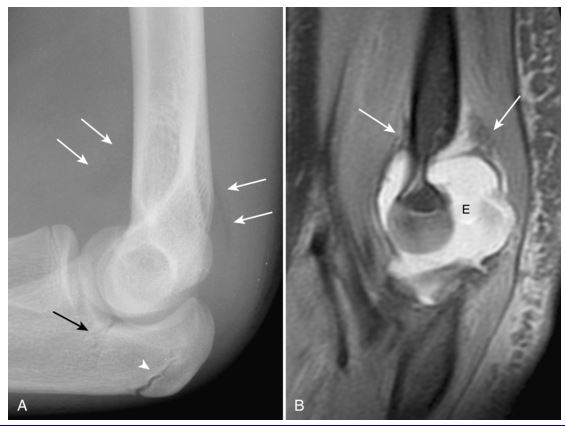

초음파 유도 전기침 치료

힘줄에 정확하게 들어가는 "침(Needle)"이 보입니다.

6주 후 치료결과를 비교해보니

"통증"** (VAS, DASH)과

"초음파 소견"

모두 호전되었습니다.

전기침 치료 후, 회복된 힘줄